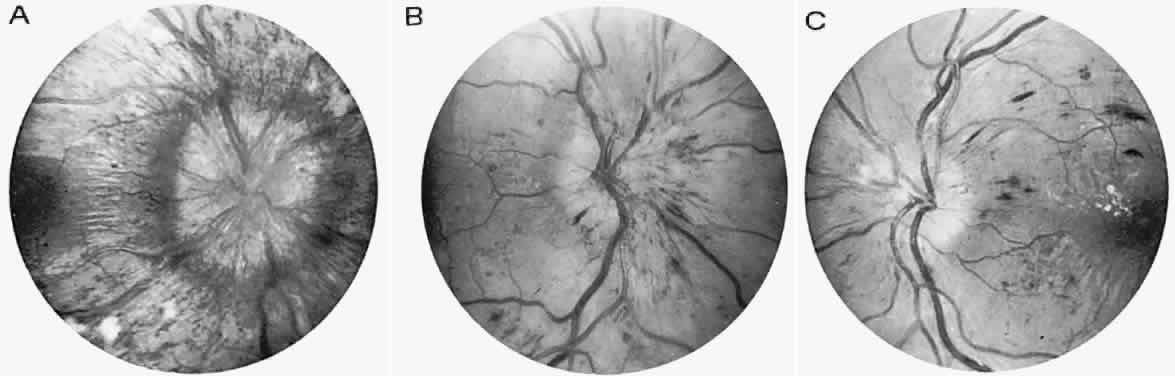

Fig. 1. A 14-year-old boy referred for occult neurologic disease or malingering who had undergone magnetic resonance imaging and psychiatric counseling. Visual acuity was 20/100 in both eyes. Fundi (A and B) show thinned rounded macular reflexes and mild pigment changes at the foveae. Fluorescein angiography (C) disclosed marked macular pigment epithelial disturbance. Diagnosis: juvenile macular degeneration (Stargardt's type).

Fig. 3. Cone-rod dystrophy or so-called “retinitis pigmentosa inversa” in a young man with progressive spinocerebellar degeneration and 20/200 acuity in each eye.